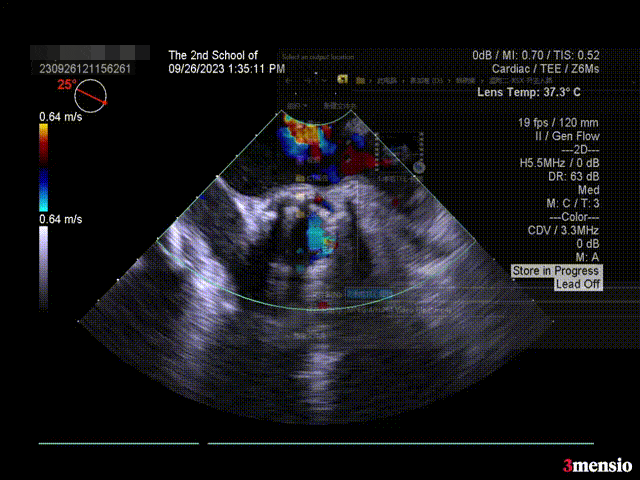

瓣膜释放后超声情况:

短轴超声

长轴超声

术后压差 5mmHg